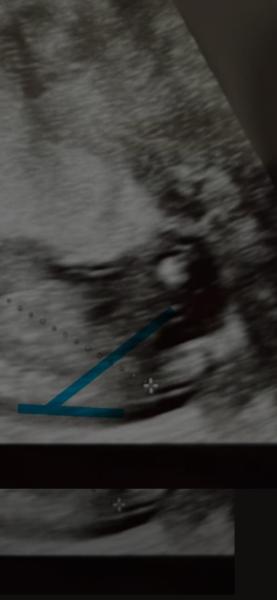

Hallo, letztendlich ist es uns egal ob Junge oder Mädchen. Aber wir sind natürlich tierisch neugierig 😁 US ist von der 16. SSW - könnt ihr etwas erkennen?

Bild zu Wer kann das Geschlecht deuten? - Schwanger - wer noch? Rund um die Schwangerschaft

Guten Abend Dimholt,  Also... Mit riiiichtig viel Phantasie und keinem gelernten Blick. Köööönnntteee ich vermuten, dass es ein Junge wird.  Es ist natürlich nur Spielerei jetzt und das Bild ist leider echt nicht optimal. Aaaaber hab dir einfach mal angezeichnet. Wenn diese beiden Striche doch der sagenumwobene Nub ist, könnte es wie gesagt auf einen Jungen hindeuten.  Und hoffe jetzt natürlich sehr, wenn du es irgendwann mal ein professionelles Outing gibt, dass du es mit uns teilst. Bin jetzt richtig neugierig 🤭 Liebe Grüße Cleo

Hallo liebe Cleo, viiiiieeelen Dank für deine Einschätzung und die Zeichnung, das ist ja interessant, auf die Idee bin ich gar nicht gekommen 😄. Laut Ramzi in meinem 1. US wäre es vermutlich auch ein Junge.    Im Oktober ist die Feindiagnostik, da werden wir es hoffentlich erfahren und dann gebe ich hier auf jeden Fall nochmal Bescheid 🩷🩵

Liebe Cleo, du hast ein super Auge und deine Einschätzung war richtig. Es ist ein Junge 🩵 In der Feindiagnostik war es gleich das Erste was unser Bub in die Kamera gehalten hat, keine Zweifel hahaha. Zum Glück sind auch alle Werte der Untersuchung top! Was eine Erleichterung.    wie verläuft es bei dir? Ist bezüglich Geschlecht schon sicher, dass es ein Mädchen ist? ☺️